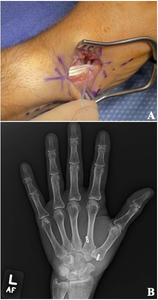

For patients with advanced pantrapezial disease, surgical management typically begins with a resection arthroplasty, first described by Gervis in 1949.3,16 The technique initially involved complete excision of the trapezium [Figure 2]. However, partial resection can also be performed. Trapeziectomy can be performed arthroscopically17 or open, and in isolation or concomitantly with an interposition or suspensionplasty.